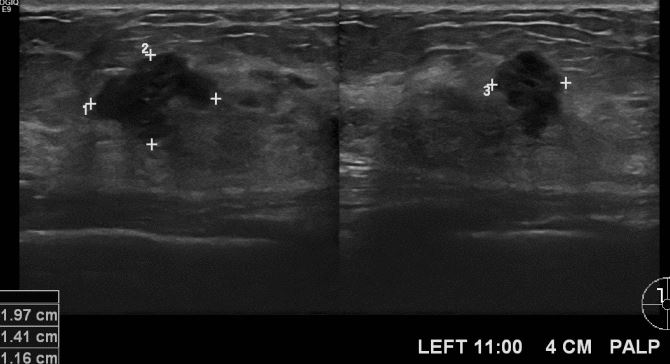

상기환자 좌측 유방에 만져지는 멍우리로 내원하신 50대 여성분으로 좌측 11시 방향에서 4cm 떨어진 거리의 만져지는 멍우리 조직검사 시행하여 좌측 침윤성 유관암 진단되었습니다.